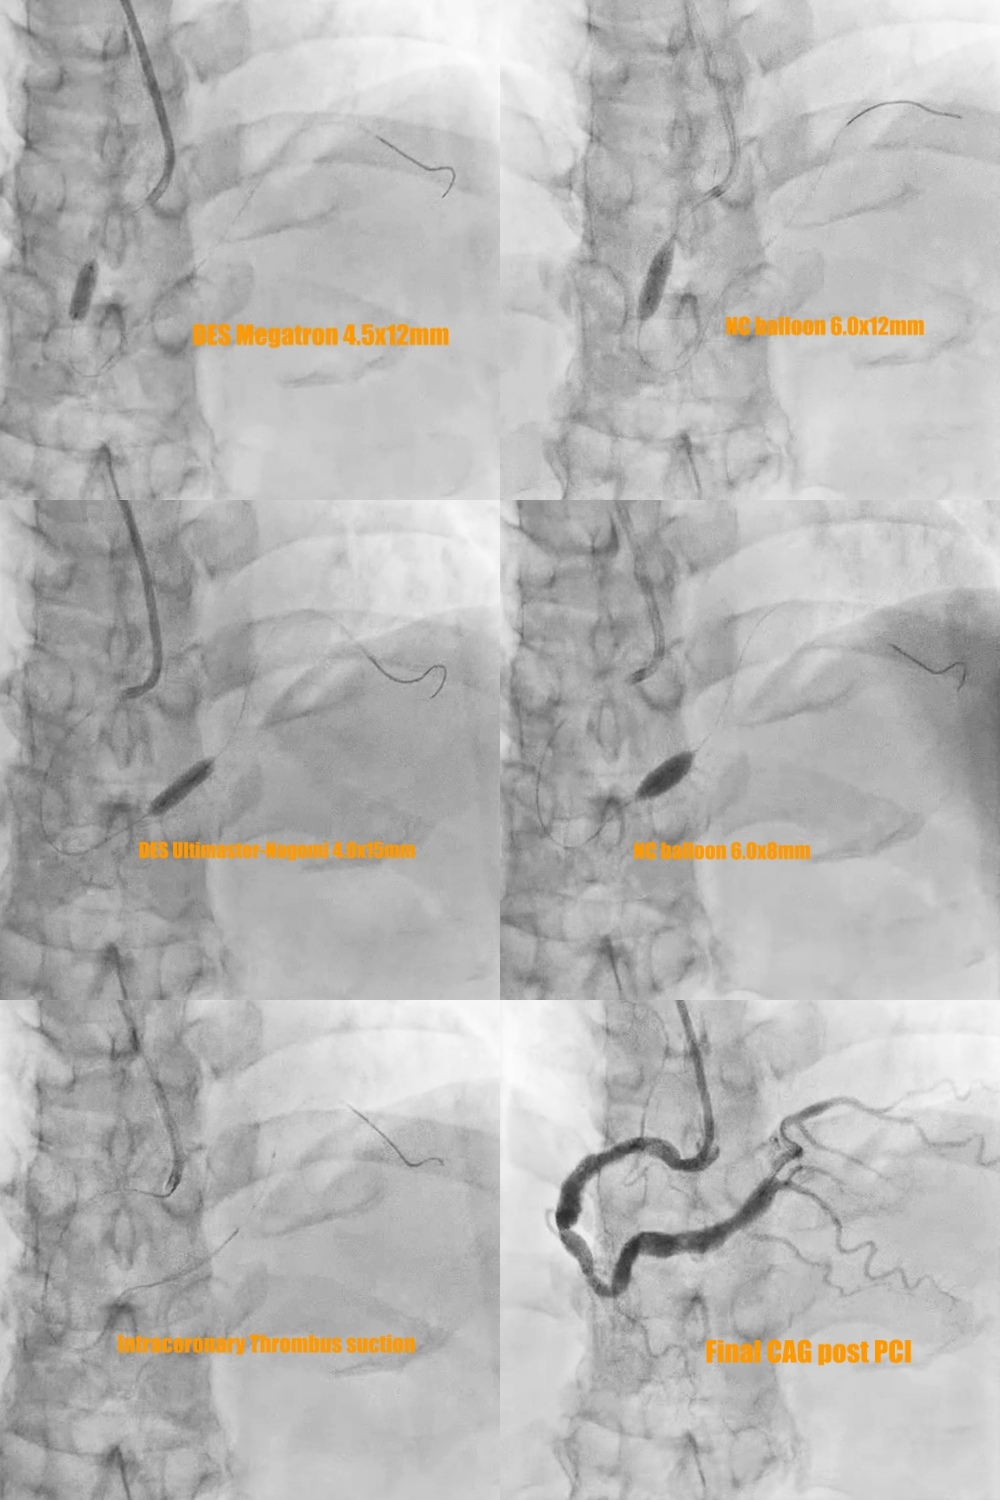

1. The 7 Fr left side radial sheath (Terumo; Glidesheath) was via left side radial artery approach and the guiding catheter was JR4 (Medtronic 7Fr) and the workhorse guidewire was Sion blue.2. Predilatation of the stenoses of distal part and middle part of RCA by the baloon Euphora 2.5x20mm and then IVUS was performed to assess the high risk plaque with adjacent CAE at middle RCA (Fig 5a and 5b) and stable plaque with adjacent CAE thrombus at distal RCA (Fig 5d and 5e).3. PCI of high risk plaque of middle RCA by direct DES stenting of Megatron (Boston ; 4.5x 12mm) under the extra-support of the guiding extension catheter of Telescope (Medtronic; 7 Fr) and lesion post-dilatation by larger balloon of NC Emerge (6.0x12mm) with 14 bars (Fig 6).

4.. PCI of distal RCA lesion first by direct drug-eluting stent (DES) Ultimaster-Nagomi (Terumo; 4.0x15mm) and then post-dilatation by larger balloon NC Emerge (6.0x8mm) with 16 bars. There was coronary thrombus at coronary ectasia of distal RCA with slow distal flow (Fig 5d). The intra-coronary thrombus suction device of Export Advance (Terumo; 6 Fr) was into CAE site of distal RCA for maneuver thrombus suction several times but still residual thrombus at CAE (Fig 6).

5. The final coronary angiogram of RCA has good distal flow (video 3) with stent optimalization (Fig 5c and 5f)